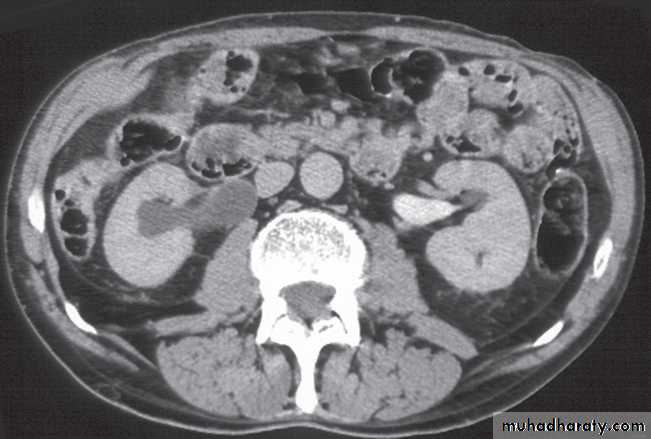

Computed tomography is now widely used to evaluate urinary tract obstruction .In acute obstruction, non-contrast enhanced CT sensitively demonstrates calculi and the unopacified, dilated collecting system can frequently be traced down to the point of obstruction .

Non-contrast CT is often used in acute ureteric colic, as an alternative to IVU, in patients with an allergy to intravenous contrast medium.

-Renal cell carcinomas are approximately spherical and often lobulated .With density similar to renal parenchyma or slightly less with often seen some areas of necrosis & calcification .

Staging of renal cell carcinoma is usually undertaken with CT, the current method of choice .